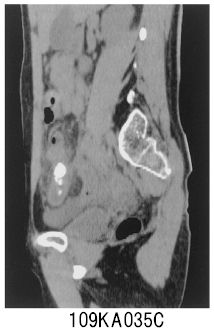

治るという前提でがんになった 情報戦でがんに克つ』高山知朗, 上腹部痛(Epigastric Pain)シリーズ10 【症例 EE 46】,

上腹部痛(Epigastric Pain)シリーズ10 【症例 EE 46】, 102D39 | 膵癌 国試 | テコプラ,

102D39 | 膵癌 国試 | テコプラ, 109A35 | 虫垂炎 国試 | テコプラ

109A35 | 虫垂炎 国試 | テコプラ商品説明

書名カナ:フクツウデワカルビョウキオナカノイジョウデガンオシル

書名カナ:フクツウデワカルビョウキオナカノイジョウデガンオシル